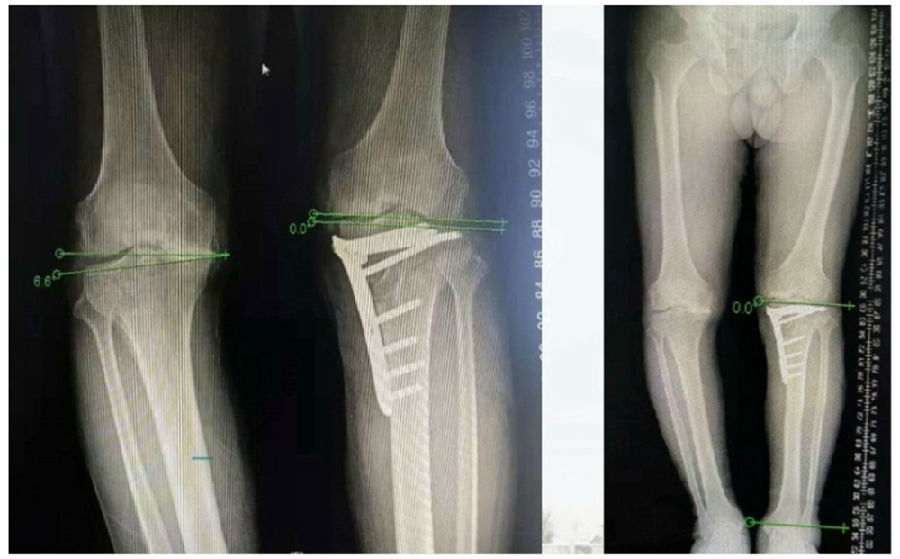

典型病例,男性,57岁,农民,左膝疼痛3年。

术前

术前影像资料

术前规划:

①关节内截骨,内外侧平台平行。

关节内截骨

②再次确定下肢力线。

确定力线

③关节外截骨。

关节外截骨

术中先打克氏针确定截骨方向,先做关节内截骨,截完后测量下肢力线,发现并没达到术前设计的Fujisawa点。

术中影像资料

随后用骨刀继续向前敲,做HTO内侧开放楔,截骨完成后内侧固定,并测量下肢力线,此时达到术前设计的要求。